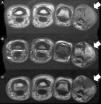

The case was a male patient, 65 years old, with no relevant medical history, who was consulted due to painless swelling on the dorsal side of the fifth finger of the left hand which had lasted for 4 years, with no history of trauma. Physical examination confirmed the tumor, elastic on palpation, with preserved finger mobility (Fig. 1) Simple X-rays showed a soft tissue tumor (Fig. 2); the ultrasound demonstrated the same lesion and the MRI showed a lesion measuring 16×10×12mm in diameter craneo-caudally, anteroposterior and transversely, unhomogeneous, with a hypointense signal and loculations on T1, predominantly hyperintense on T2 and showing moderate contrast enhancement (Fig. 3).

The lesion was diagnosed to be a giant cell tumor of the tendon sheath of the fifth finger and was removed in its entirety (Fig. 4). Two years later the lesion recurred (Fig. 5) and the patient underwent surgery. Currently, after two years, there have been no new recurrences, the mobility of the distal interphalangeal joint is limited, although the function of the patient's hand is normal.